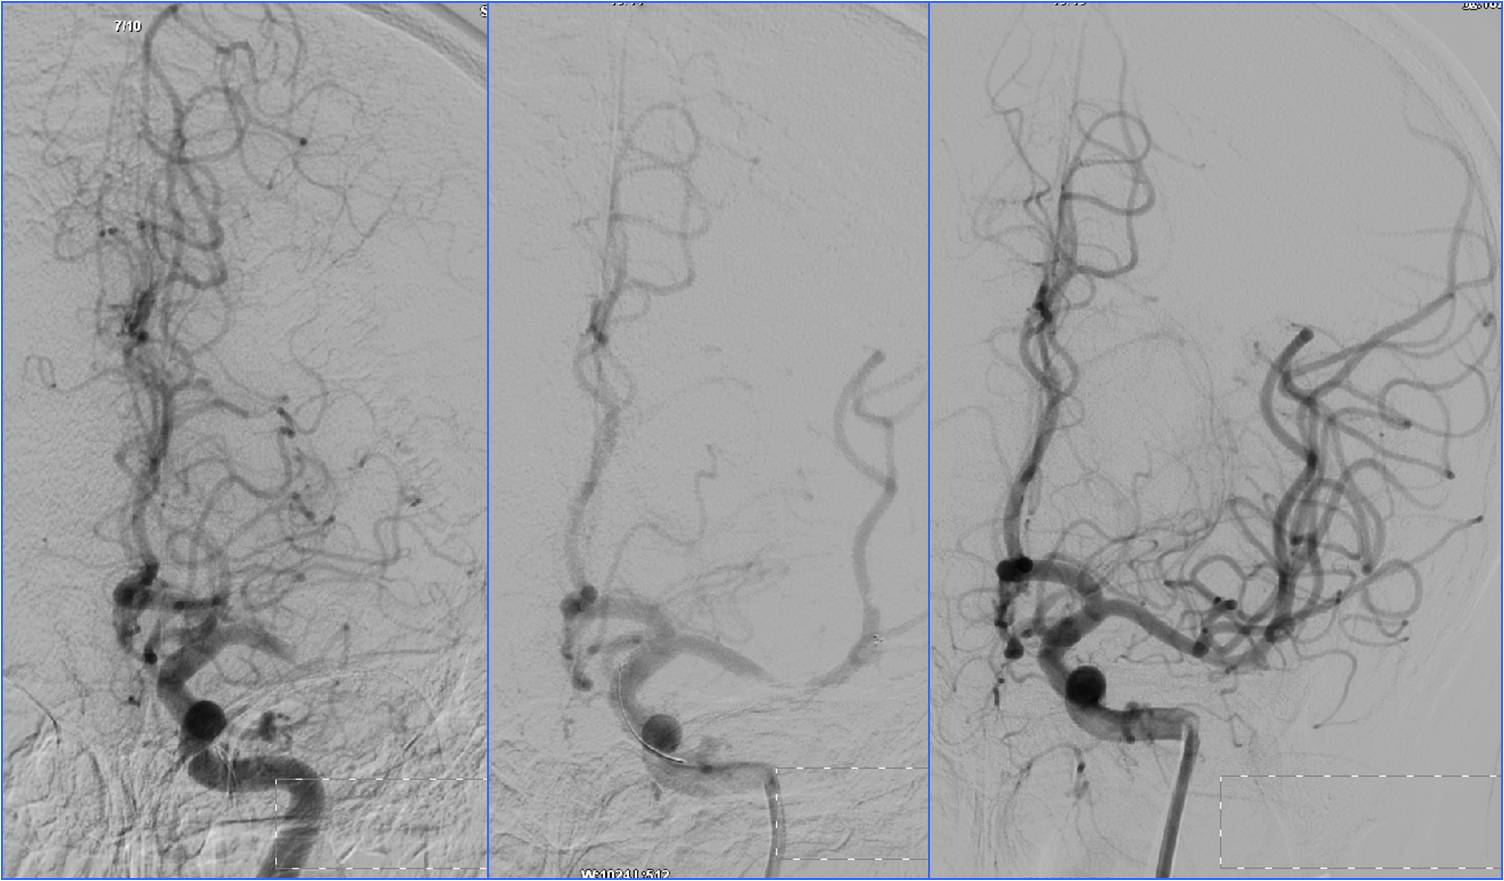

Case3 椎动脉开口支架置入

》男,68岁,有长期吸烟史。

》6:30突发晕厥1次伴头晕,7:00到急诊。7:30突然发作肢体抽搐伴意识不清。于8:10收入神经内科ICU。

》查体:血压140/60mmHg。中度昏迷,双侧瞳孔散大,光反应消失。四肢肌张力增高,去脑强直状态。双侧巴氏征阳性。NIHSS评分35分。

》昏迷前头CT检查(7:22)未见明显异常。

》昏迷后行头MRA检查。

▼7:22头CT

▼8:36头MRA

》急查血常规、凝血四项、肝肾电糖。

》签署静脉溶栓+动脉溶栓治疗知情同意书。

》8:54给予阿替普酶静脉溶栓,5mg静推,余45mg持续泵入。

》10:00股动脉穿刺。行气管插管全身麻醉。

▼于基底动脉远端及双侧大脑后动脉,分次给予阿替普酶共计5mg。

》12:10结束手术,带气管插管返回神经内科ICU。给予乌拉地尔持续泵入控制血压在110/70mmHg左右。

》第二天6:00出现中枢性高热,体温40℃。3天后转入普通病房。

》20天后出院,NIHSS评分5分。

▼溶栓后MRI